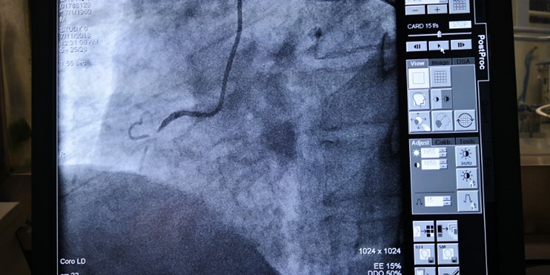

在心内科主任、胸痛中心负责人熊春林的带领下,胸痛中心介入团队紧密配合,手术顺利进行。造影证实患者发病的罪魁祸首是血管右冠近段完全闭塞,医生们立即送入导丝、球囊开通血管,并成功植入支架1枚,使患者转危为安。

造影提示右冠近段完全闭塞